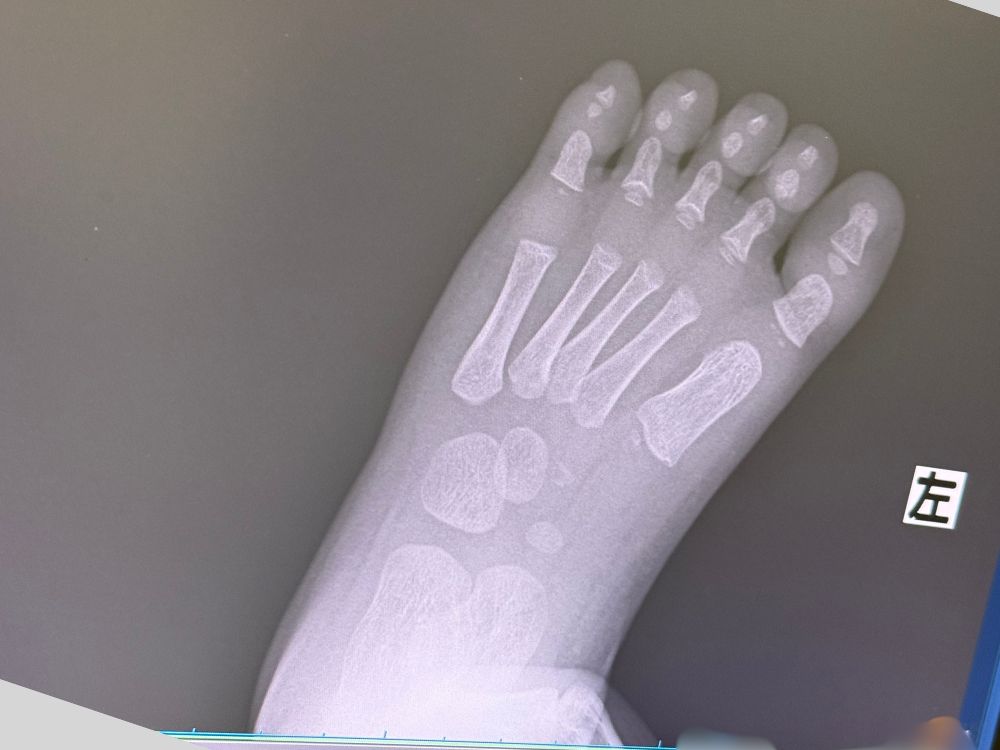

念のためレントゲンを撮ってもらい、結果は「骨折ではない」とのこと。

でも、受診したことでとても安心することができました。そして可愛い足の骨を見ることができました(笑)。